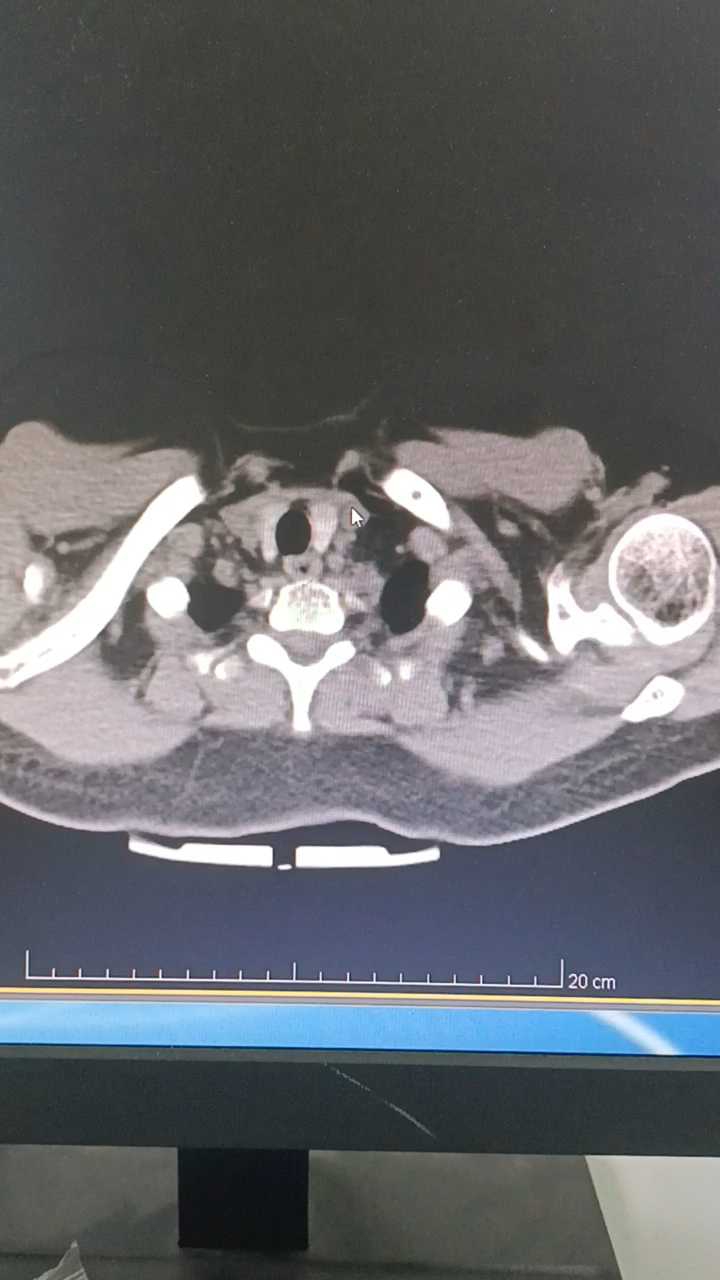

中年女性,反复咳嗽咳痰伴气促2月余,无发热畏寒等不适。既往有高血压病史。

胸膜下多发结节,周围晕征,支气管半入征,影像考虑隐球菌吗?求教各位老师,纤支镜灌洗液提示肺链,流感嗜血杆菌与影像相符吗?@唐绍宏 @李小平主任 @秒天秒地秒空气 @涂涂呼吸 @李梦杰huxi